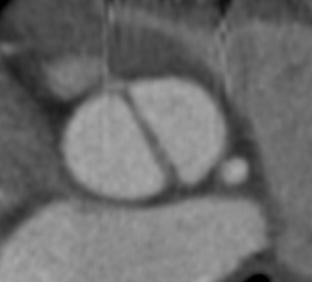

O implante transcateter de válvula aórtica (TAVI) para o tratamento da estenose aórtica, segundo as principais diretrizes atuais, é indicado como uma alternativa ao tratamento cirúrgico convencional n…

O implante de prótese valvar aórtica por cateterismo (TAVI) para o tratamento da estenose aórtica calcífica é uma realidade nos dias atuais, com evidencias científicas sólidas, estudos clínicos robust…